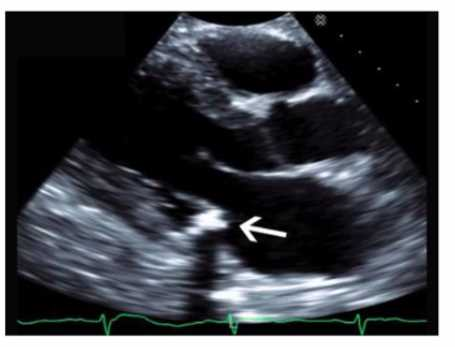

Which echogenic structure is indicated by the arrow on this image?

The image is a parasternal long-axis echocardiographic view focusing on the mitral valve annulus with a highly echogenic, dense, and well-defined structure located at the base of the posterior mitral leaflet. This appearance is characteristic of mitral annular calcification (MAC), a degenerative process resulting in calcium deposition along the mitral valve annulus.

Vegetations appear as irregular, mobile masses attached to valve leaflets and are less dense. Tumors and thrombi have different echogenicity and locations (tumors often in atria, thrombi in atrial appendages). MAC is usually more echogenic and localized to the annulus.